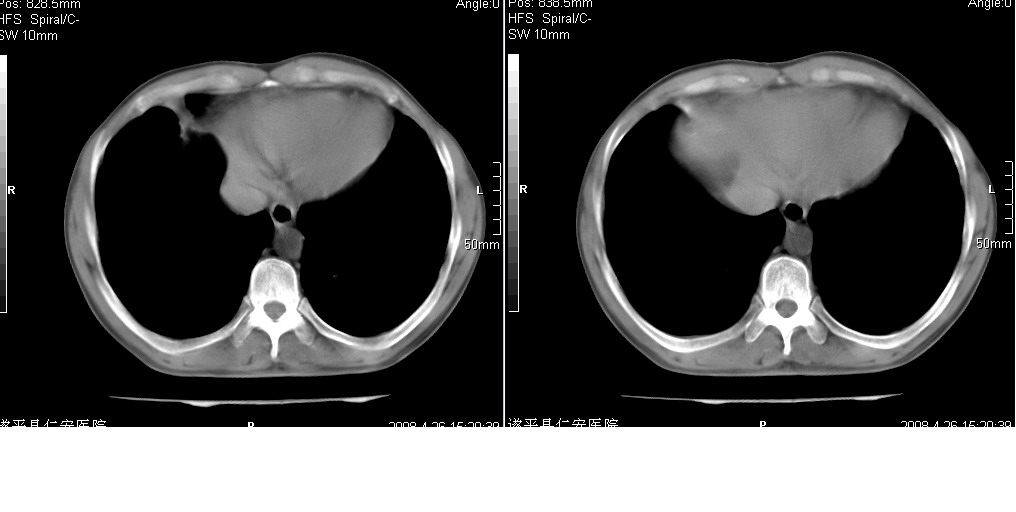

以下是引用随光逐影在2008-4-27 20:49:00的发言:[br]考虑为:1)右肺中叶及左侧下叶感染性病变。2)左肺下叶支气管扩张?建议:抗炎治疗后复查。